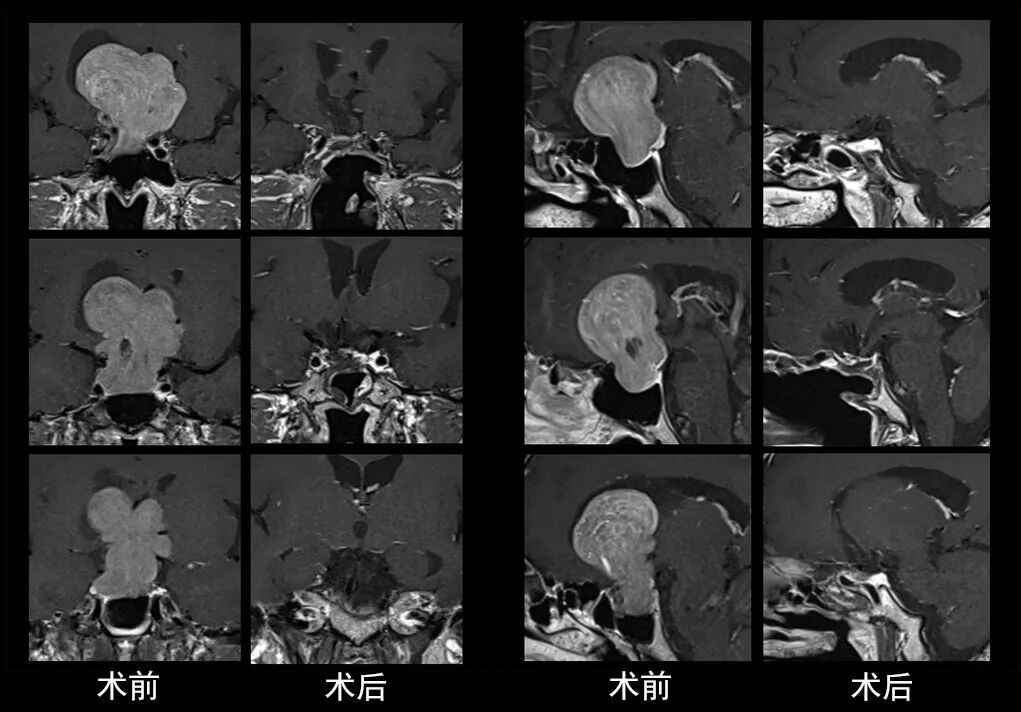

本研究中采用联合手术策略的代表性病例展示:

case 1

case 2